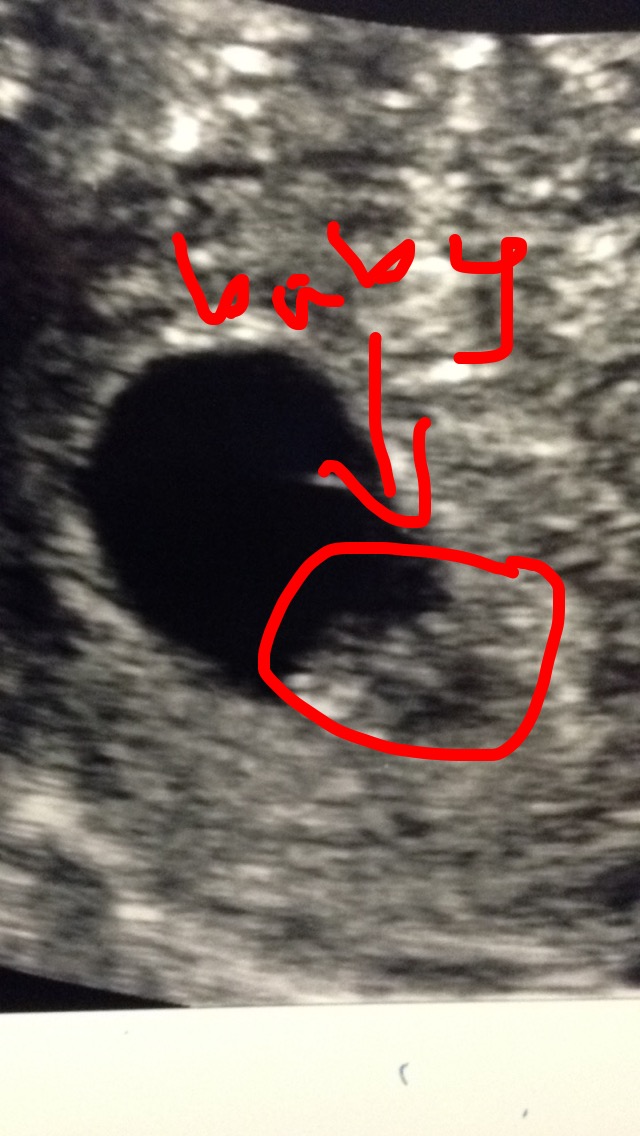

It was pretty dang cool seeing the blob inside me on the first ultrasound. The movement I first detected got me excited, then my doc reminded me that was actually my lunch moving through my intestine. Sorry, baby, to confuse you with food!

But when she found the embryo she told us to look for a flutter. It was lighting fast, but there it was…the first signs of a beating heart! Miraculous. I cannot get over how quickly the most complex parts of the human anatomy take shape.